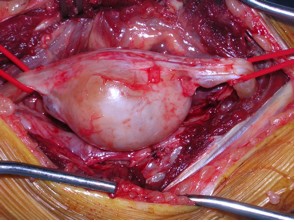

Liposarcoma is a malignant tumor that arises from mesenchymal cells (specifically, abnormal fat cells in deep soft tissue that multiply in an unregulated manner), mainly affecting middleage people at sites such as the thigh, gluteal region, retroperitoneum, and leg and shoulder area Occasionally, the liposarcoma can become very large. Sifontis NM, Coscia LA, Constantinescu S, et al Pregnancy Outcomes in Solid Organ Transplant Recipients With Exposure to Mycophenolate Mofetil or Sirolimus Transplantation 06;(12) PubMed. Il liposarcoma è un tumore del tessuto connettivo, in particolare delle cellule adipose ne esistono diverse varianti (3) ben differenziati, mixoidi, e a cellule rotonde la loro aggressività dipende al tipo al quale appartengono, alcuni sono aggressivissimi e metastatizzano facilmente, altri sono indolenti e poco aggressivi è "normale" che sia così grande perchè di solito i liposarcomi.

It is very frequent and can reach a considerable size Differentiation between lipoma and liposarcoma of low grade malignancy represents an important diagnostic problem, and valuable help in the differential diagnosis is provided by ultrasonography (US), computed tomography (CT), magnetic resonance imaging (MRI), biopsy and/or. La localizzazione di partenza è quasi sempre profonda, a livello dei setti intermuscolari (in particolare per la coscia sono sedi preferenziali il m quadricipite e i m abduttori), o dai tessuti periarticolari, o dal grasso perirenale nei casi di liposarcoma retroperitoneale (5), Friedman e Egan (lO), Perry e Che (25), Edland (4), Mc Neer e. For 30 years, Karen Minish has been sharing her gifts with the Bow Valley making us all the richer for it From sharing her incredible voice as a soloist with the Bow Valley Chorus, bringing Christmas joy through her carolling quartet, conducting the hospital choir in Banff, performing, or creating and directing the annual BVC Variety Show, creating incredible works of art, sharing her.

Giant Lipoma Of The Thigh A Case Report Sciencedirect